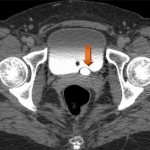

The operation of a computed tomograph is based on X-ray pulses. The waves emitted by the beam tube pass through the patient's body and are captured by the scanner's sensors. Darkening in the lungs visualized on X-ray layer-by-layer images will indicate the presence of pathology. Information from the scanner is processed by a computer and as a result, the patient receives a sheet with layer-by-layer images of the organ being examined.

CT scan of the lungs - what it shows

CT scan of the lungs is a method designed to clarify the characteristics of the pathology, which is revealed on the X-ray of the chest, but does not allow making a diagnosis. An X-ray image is obtained by summation of shadows located along the path of the X-ray beam. Behind the sternum there is a whole complex of organs that are not diagnosed on a chest x-ray. More precisely, minor anatomical changes and enlarged intrathoracic lymph nodes are visualized when performing a CT scan of the chest. It is rational to perform a computed tomography scan if hilar lymphadenopathy is suspected. The radiologist can visualize a lumpy enlargement of the roots of the lungs in the image. This is where the capabilities of the traditional x-ray method are limited. A CT scan of the lungs and mediastinum allows a thorough study of the size and structure of enlarged lymph nodes. With tuberculosis of the intrathoracic lymph nodes in children, radiography does not show pathology due to the projection overlap of the sternum and heart. Computed tomography clearly indicates the pathological nature of the lymphadenopathy. It is not always necessary to do a CT scan of the lungs. Due to the high radiation exposure of the patient, it is necessary to be selective in prescribing the diagnostic method. In case of traumatic injury to the chest, a computed tomography scan is often prescribed. There are clinical studies regarding the irrationality of prescribing the procedure for blunt chest trauma. Researchers from California and Massachusetts conducted thorough studies to evaluate the possibility of not using computed tomography for this nosology. CT scans increase the likelihood of cancer in young people due to the mutational effects of ionizing radiation on cells. The cost of analysis is not cheap. Professor, MD R. Rodriguez from San Francisco (University of California) conducted a study involving about 11 thousand people over 14 years of age. About 5,000 people had an unknown diagnosis. Sorting of injuries was carried out according to the following gradation: